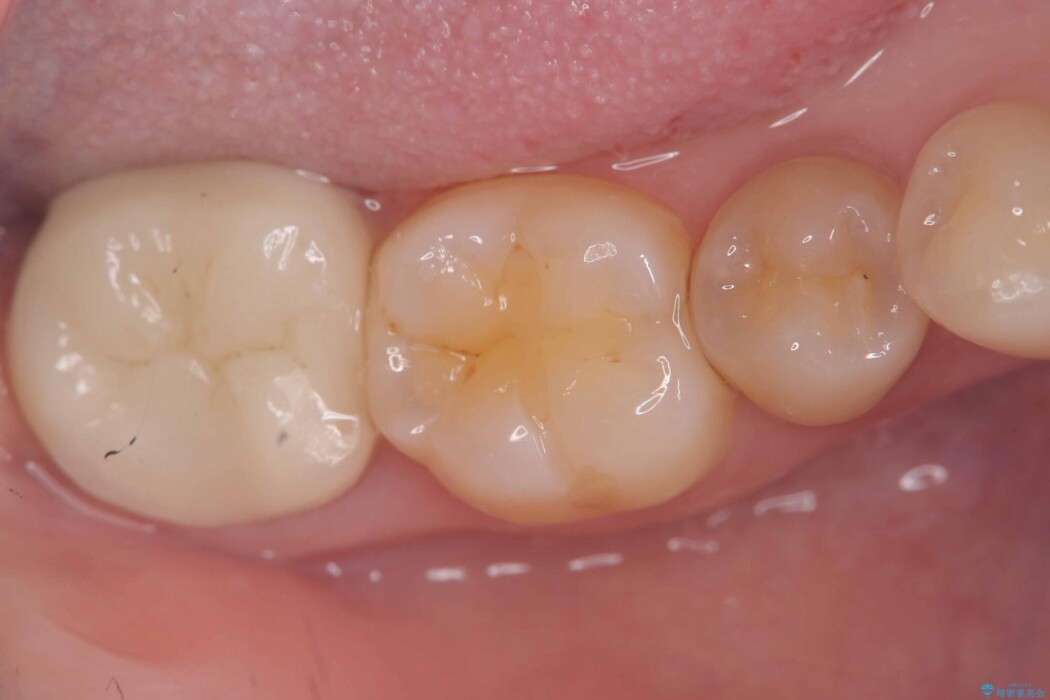

治療後について

クラウンにすることで、歯全体を保護しながら、見た目も自然で長期的に安定した状態を維持しやすくなります。

「できるだけ歯を削りたくない」という考えも大切ですが、状態によっては、長持ちさせるためにあえて全体を覆う治療が適している場合もあります。